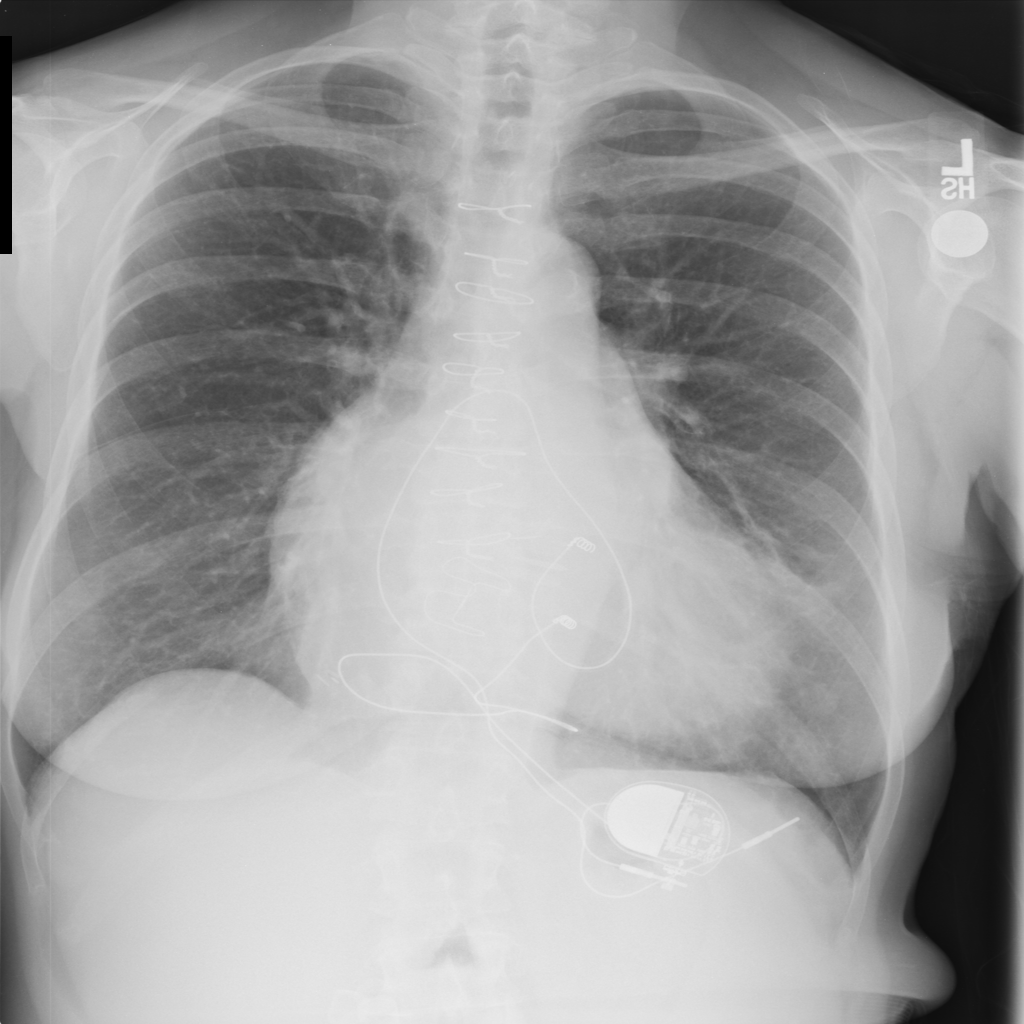

PAT-AE5C · IMG-000Cardiomegaly

PAT-AE5C · IMG-000

PA